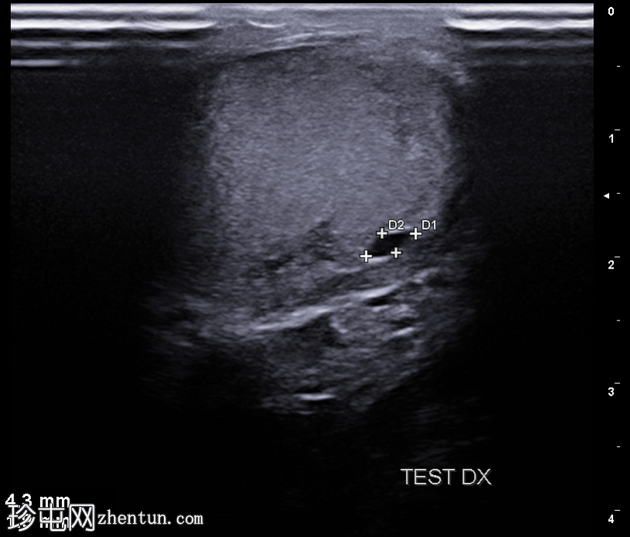

左侧阴囊

疼痛

患者的

超声

检查结果。

纵切面

右侧睾丸内可见一单房性、无回声、边界清晰的病变,囊壁薄而光滑,无彩色多普勒血流信号(未显示)。

睾丸内囊肿是良性、边界清晰的无回声病变,后方回声增强,周围包绕正常睾丸实质。大多数睾丸内囊肿无症状,位于睾丸纵隔附近。随访期间,该病变多年来保持稳定。